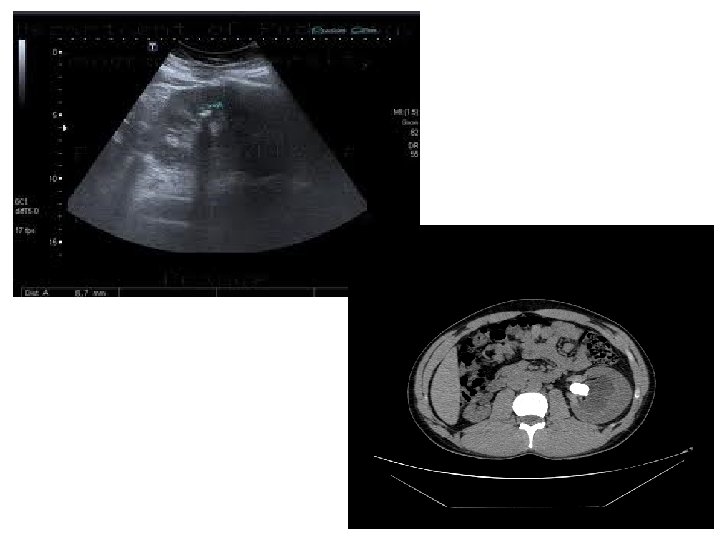

US • Use high frequency sound wave. • Contrast between tissue is determined by sound reflection.

US Image features: • • Operator dependant. Projectional image. Good resolution. Used for stone, hydronephrosis, focal lesion.